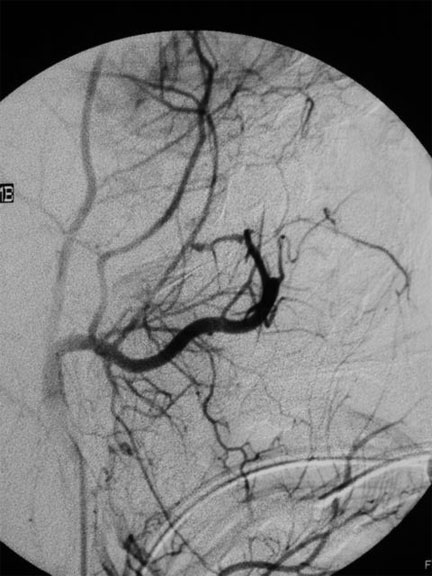

CASO 1 : Embolización del angiofibroma nasofaringeo juvenil Antes del tratamiento de embolización Despué del tratamiento de embolización